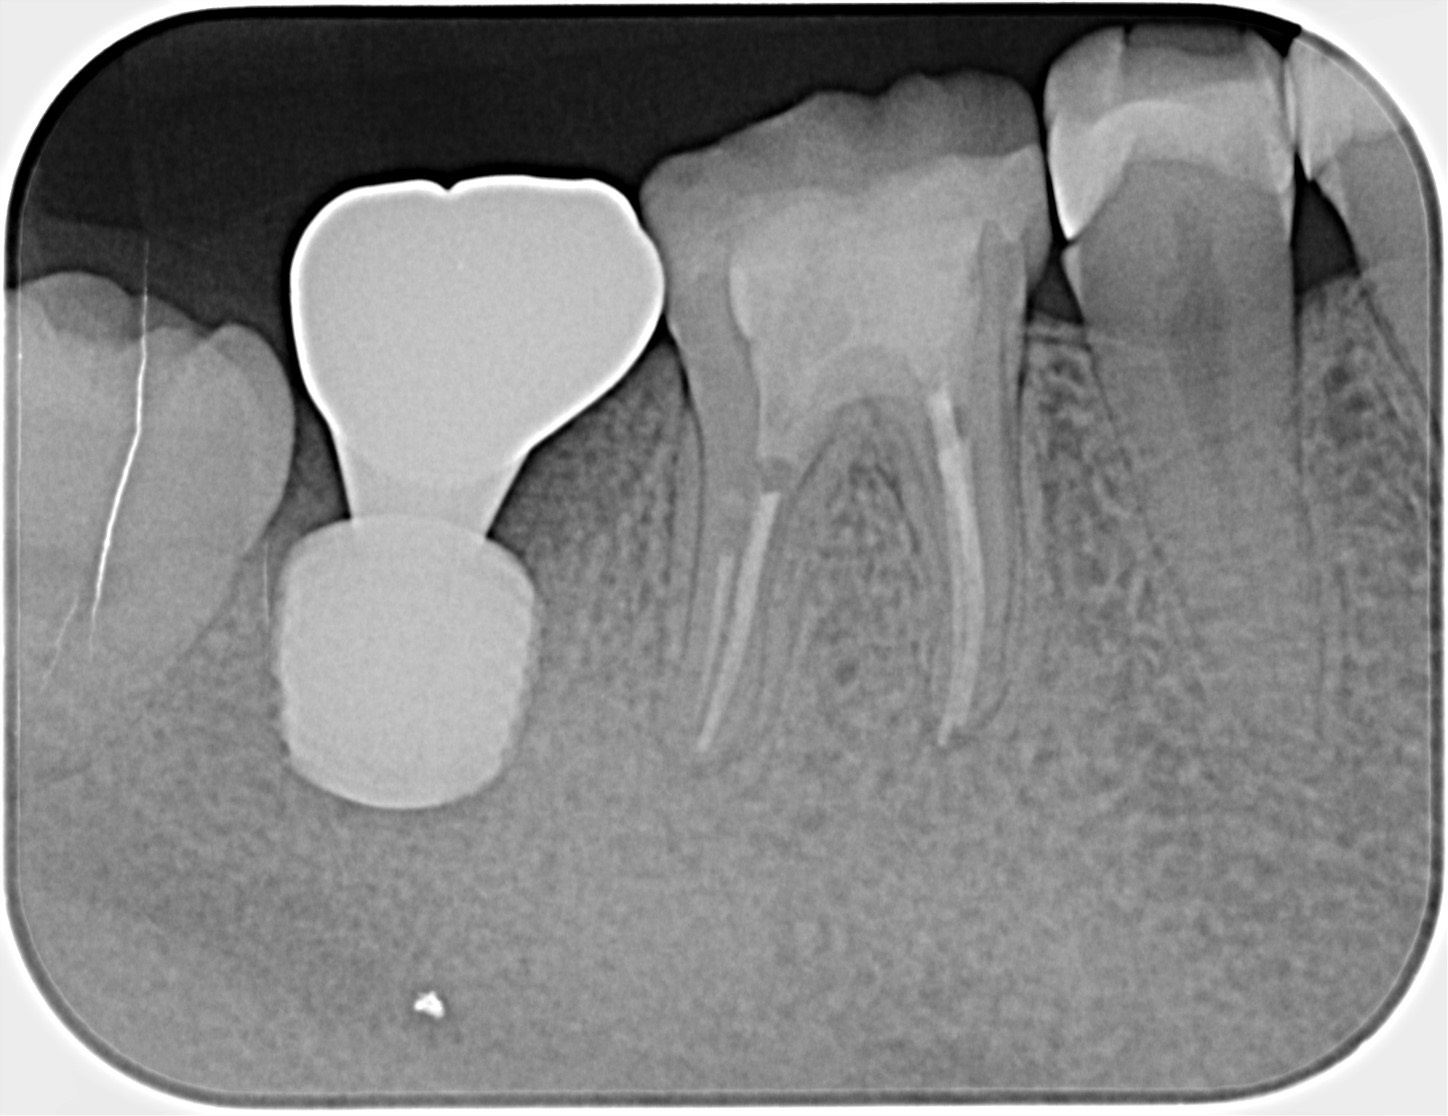

30代、女性、右下に違和感があることを健診中に申され、インプラント治療を行いました。

| 患者様の主訴 | 右下に違和感がある |

| 診断結果 | 右下7番歯根破折 |

| 治療内容 | 抜歯即時インプラント |

| 治療期間 | 8週間 |

| 治療費用 | ¥539,000(税込) |